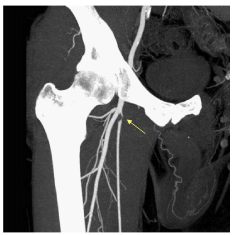

Ces techniques non invasives permettent une cartographie préthérapeutique souvent suffisante pour envisager un geste de revascularisation endovasculaire ou chirurgicale (figures 38.1 à 38.3). Les deux techniques ne nécessitent pas de ponction artérielle et l’angio-IRM ne nécessite pas d’exposition aux rayons X, ni l’utilisation de produits de contraste iodés.

Fig. 38.3 Exemple d’angioscanner des membres inférieurs montrant un rétrécissement localisé de l’artère fémorale immédiatement en aval de la naissance de l’artère profonde de la cuisse avec une hypertrophie compensatrice de cette dernière.

Source : CERF, CNEBMN, 2022.

Les techniques d’angio-IRM (cf. figures 38.1 et 38.2) ou d’angioscanner (cf. figure 38.3) mettent en évidence des sténoses ou des occlusions artérielles ainsi que le développement de voies de dérivation pour compenser l’hypoperfusion en aval.

Les différences entre les deux sont les suivantes :

- les calcifications artérielles ne sont pas visualisables en IRM ;

- l’angio-IRM a tendance à légèrement surestimer les degrés de sténose ;

- les plaques athéromateuses sont parfois mieux analysées en angioscanner grâce aux reconstructions dans l’axe des vaisseaux.